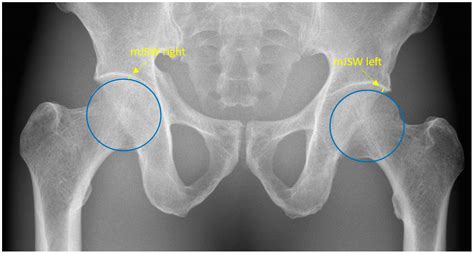

Radiologists use specific measurements and comparisons to assess the hip joint. For example, the Sharp angle and the center-edge angle are commonly used to evaluate the acetabular coverage of the femoral head. These angles help determine if the hip joint is properly aligned and functioning correctly.

• Joint Space: The space between the femoral head and the acetabulum should be uniform and well-defined. Narrowing of this space can indicate arthritis or other degenerative conditions.

• Alignment: Proper alignment of the femoral head within the acetabulum is crucial. Misalignment can suggest dislocations, fractures, or developmental issues.